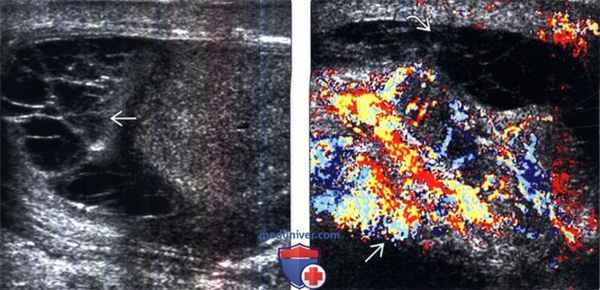

(Слева) УЗИ мошонки в сагиттальной плоскости: у мужчины 19 лет, поступившего с лихорадкой и острой болью в мошонке, определяются линейные тяжи гноя В во влагалищной оболочке. Этот признак характерен для пиоцеле.

(Справа) Энергетическая допплерография в сагиттальной плоскости: у этого же пациента определяется гиперемия придатка и яичка (признаки эпидидимо-орхита).

(Слева) УЗИ, в сагиттальной плоскости В-режим: у мужчины 37 лет, поступившего с острой болью в мошонке, лихорадкой и дизурией, определяется крупное пиоцеле с бесчисленными перегородками.

(Справа) Цветовая допплерография придатка в сагиттальной плоскости: у этого же пациента определяется гиперемия придатка, а также расположенное по соседству пиоцеле.